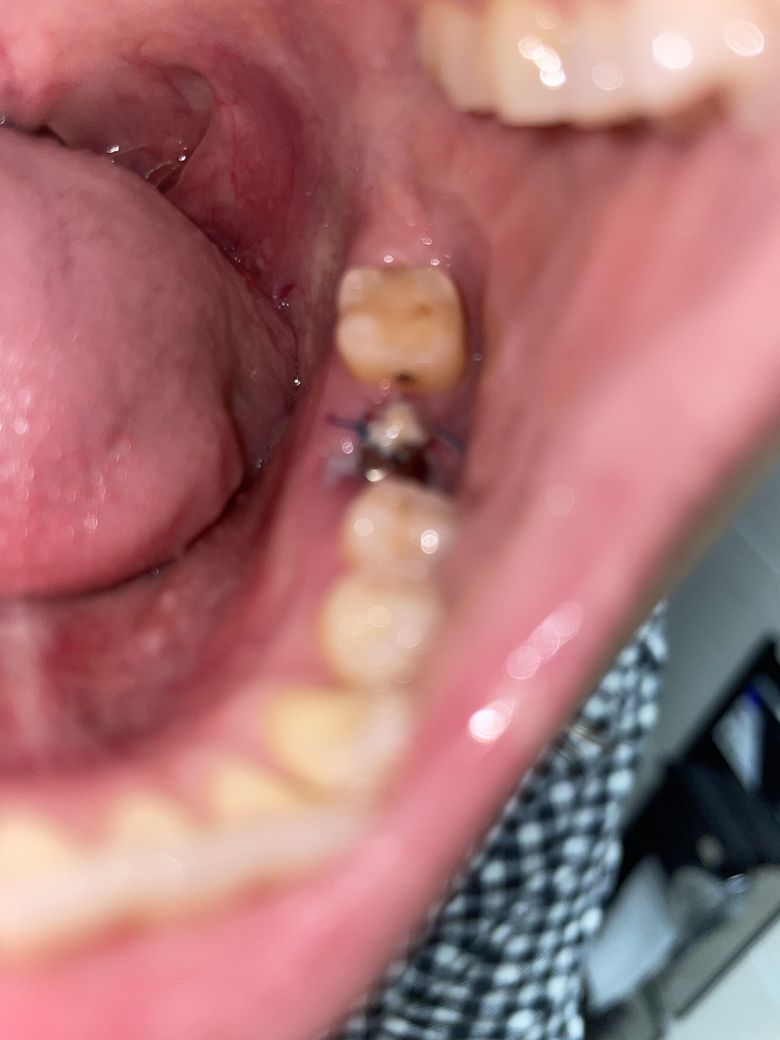

잘 아물고 있는건지 궁금합니다. 걱정되요

혹시나 안좋은건지 염증이 생긴건지 궁금해 이렇게 여쭤봅니다 오늘은 또 안에 하얀게 더 생긴느낌인거같고...아무는건가요?염증인가요?

• 그다지 문제는 없어보이며 하얀막이 생기면서 낫는 것이 정상입니다.

통증이 심하거나 붓기나 출혈이 다시 심해지는 경우엔 치과 가보셔야 합니다.

• 사진으로 보아서 전혀 문제점은 보이지 않습니다. 따라서 다음 실밥 제거일에 치과를 방문하여 검진을 받으시면 될 것으로 보입니다.

정진석 치과의사 드림

• 잇몸 부위가 아물고 있는 과정으로 보입니다. 잇몸이 완전히 암흐르기 위해서는 2주에서 3주 가량 걸리기 때문에 그 이전까지 해당 부위를 자극하지 않는 것이 좋습니다. 들춰서 확인하는 행동 또한 해당 부위에 자극을 할 수 있습니다. 자세한 확인을 위해서 치과에서 진료를 받아보는 것을 권유드립니다.

• 안녕하세요 치과의사 김철진입니다. 발치를 하고나면 잇몸이 치유되는과정중에 자연스럽게 생기는 현상이니 문제가 잇는건 아닙니다. 걱정하지 않으셔도 될것같습니다 .

1. 사진이 흐릿하여 정확히 보이진 않으나 특별히 치유 부전의 양상은 아닌 것 같습니다.

2. 음식물찌꺼기나 이물질이 끼어있지 않도록 양치질 살살해서 잘 빼주시기 바랍니다.

3. 발치 후 주의사항 잘 지키시면 회복에 큰 문제는 없을 것입니다.